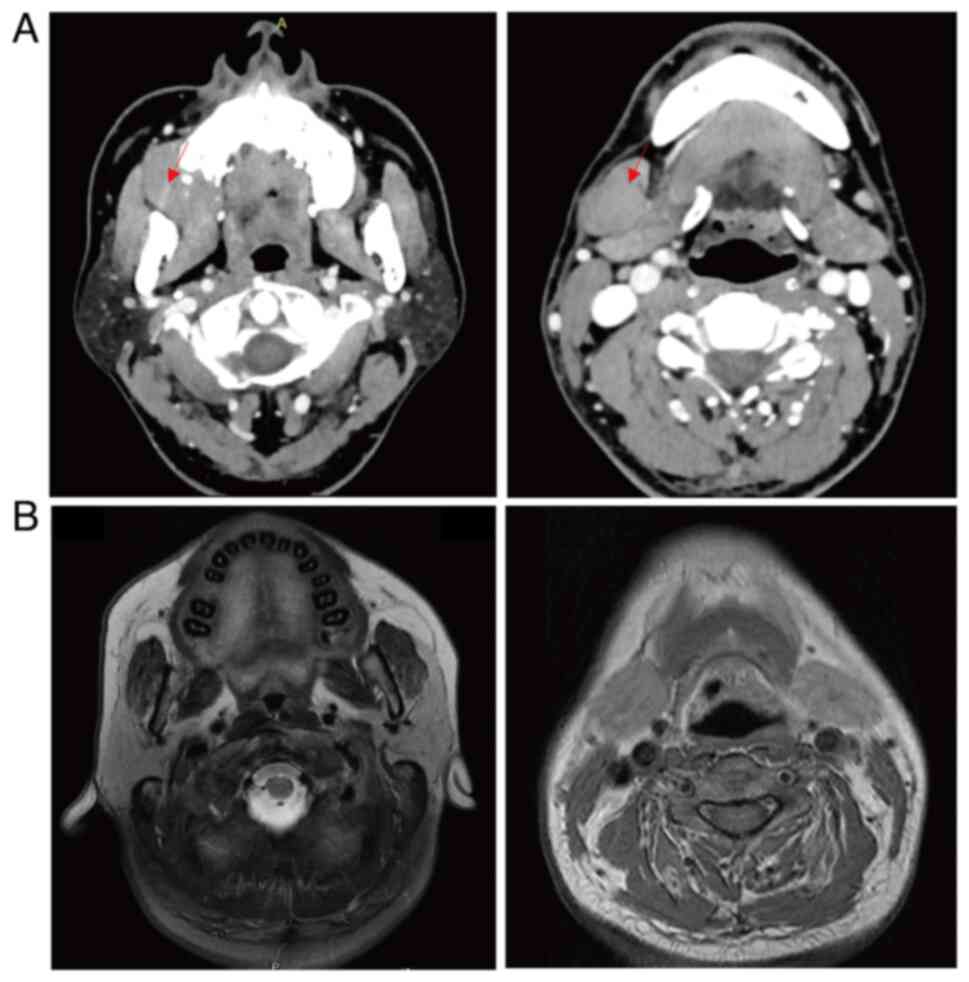

Primary gingival diffuse large B‑cell lymphoma (DLBCL) with muscle invasion is rare and accounts for ~0.5% of all reported cases of extranodal lymphoma. The present study describes the case of a 49‑year‑old man that initially presented at Yingshan County People's Hospital (Nanchong, China) in August 2017 with a chief complaint of tenderness and swelling of the jaw. Computed tomography revealed a mass in the gingiva, and enlarged lymph nodes in the cervical, mediastinal and gastro‑hepatic ligaments. Histological examination indicated the gingival mass was a DLBCL, which was positive for CD20, BCL‑6, BCL‑2, C‑MYC and MUM1. The patient received three lines of anti‑neoplastic therapy (R‑CHOP, R‑CHOEP and SYHX1903) and achieved stable disease for 6 years. Subsequently, the patient experienced trauma in the left forearm due to a car accident and the subsequent color Doppler imaging led to a diagnosis of muscular hematoma; however, magnetic resonance imaging and biopsy of the forearm muscle confirmed DLBCL invasion. Due to the patient suffering from heart failure after the third line of the previous chemotherapy, palliative radiotherapy was administered to the left forearm, and the patient achieved a partial response. In conclusion, primary gingival DLBCL with muscle invasion is rare and easily misdiagnosed, and individualized treatment should be considered for these complex cases.

Figure 1